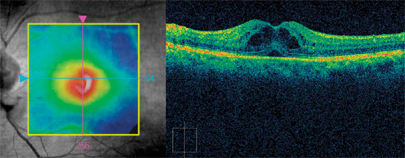

In another case, Cirrus HD-OCT helped establish a correct clinical diagnosis. A 66-year-old man underwent uneventful cataract surgery in his left eye, although he experienced only partial visual recovery from 20/100 to 20/70. Clinical examination suggested vitreomacular traction and possible macular hole formation, which was readily confirmed with Cirrus HD-OCT (Figure 3).

Figure 3. High-definition OCT shows vitreomacular traction with the appearance of a possible macular hole post cataract surgery.